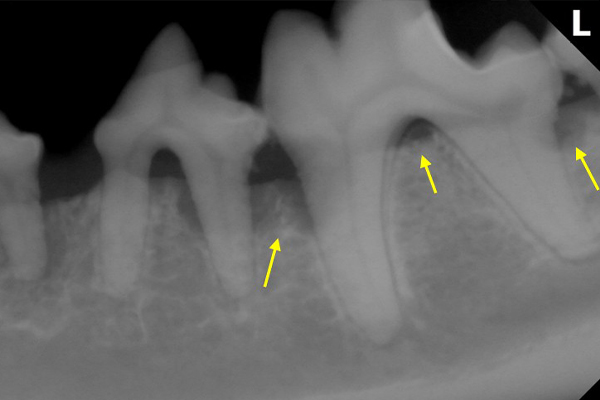

治療前

矢印の部分は、SRPの質が結果を大きく左右するため、エルビニウムレーザーを使用

治療後12か月

良質なSRP(スケーリング・ルートプレーニング)の結果、骨が再生された。